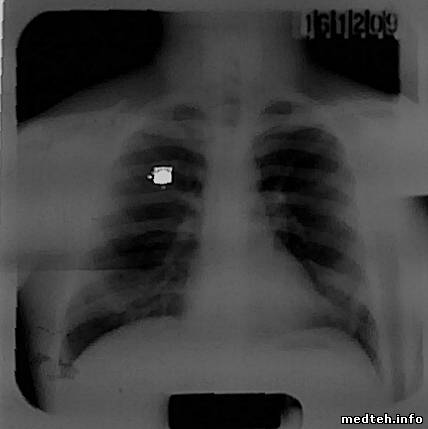

Вот 2 снимка сделанных сегодня.

Снятые люди худенькие, режим съёмки 90 КV 60 МАС и ток трубки при съёмке 102 и 100.

Что можно сказать о снимках?

Белые квадраты, это отблеск светодиода камеры сотового телефона при съёмке снимка.

снимок по степени почернения считаеться норма - если видно 3-4 верхних позвонка, качество должен оценивать рентгенолог

Показал сегодня снимки знакомому рентгенологу, который специализируется именно на флюорограммах, в другой организации.

Снимки были признаны годными, с небольшими замечаниями.

Некоторая небольшая нерезкость, и отсутствия номера карточки снимаемого.

Номер на карточке просто не писали, но проверить надо конечно,

а нерезкость, возможно, от шевелёнки снимаемого или я его неправильно поставил.

Снимали сами, рентгенлаборант уволилась, возможны варианты...